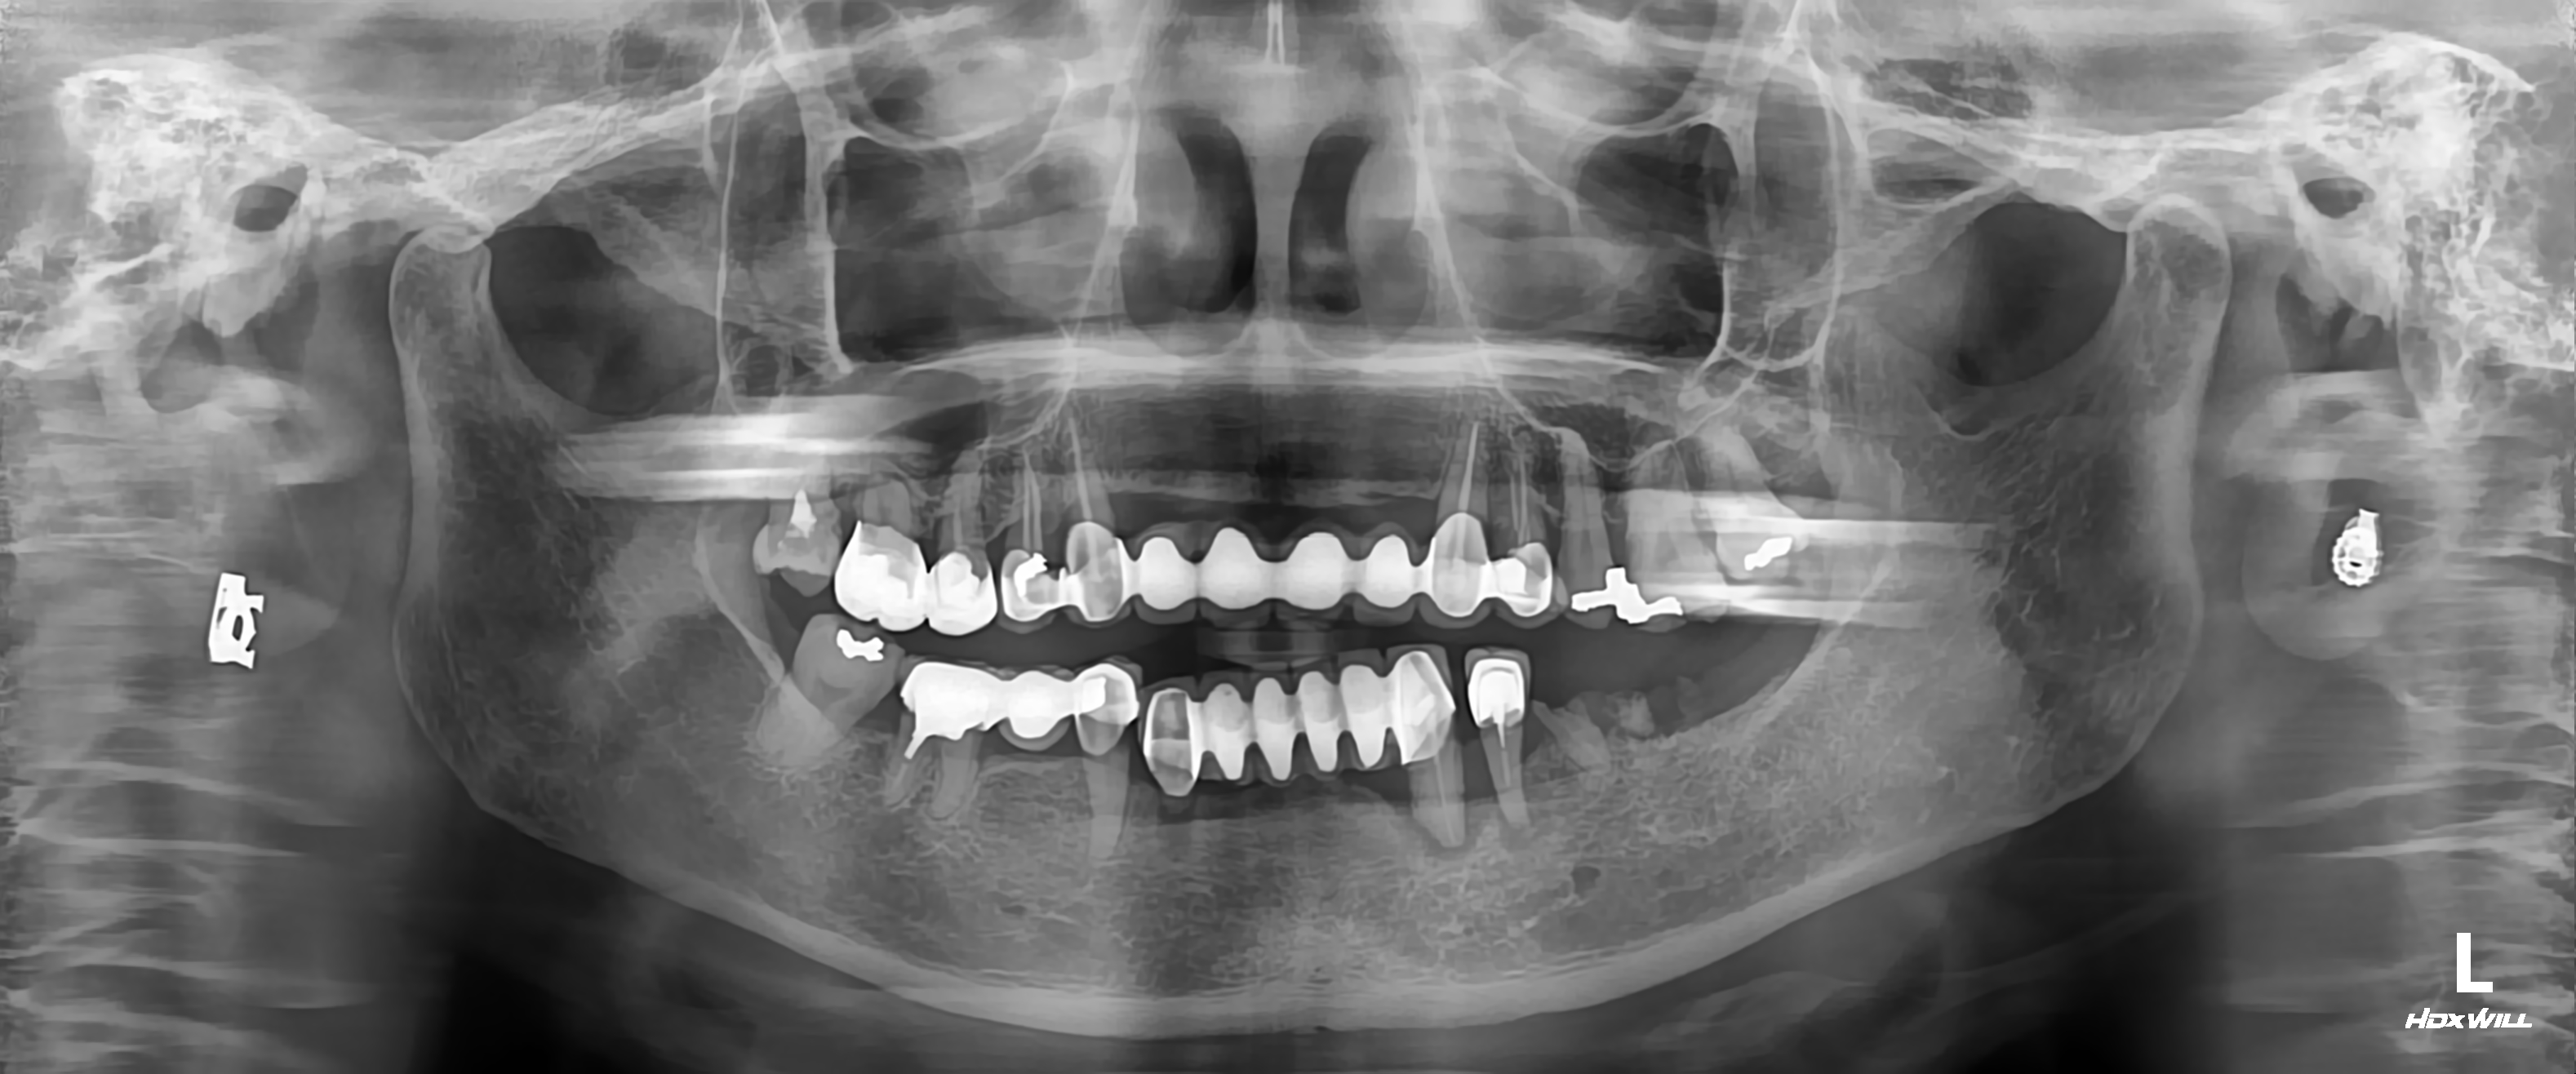

• CASE 58

치료전

임플란트 치료 후

[임플란트] 치주염으로 이가 다 흔들려서 오신 환자 케이스

"오른쪽 윗니가 다 흔들려요. 왼쪽 아래쪽 어금니에 큰 염증이 생겼어요"…

치료전 임플란트 치료 후

"오른쪽 윗니가 다 흔들려요. 왼쪽 아래쪽 어금니에 큰 염증이 생겼어요" 이 환자분은 우측 상악쪽 치주염으로 치아가 모두 흔들리고 왼쪽 아래 어금니 브릿지 부위에는 잇몸뼈가 다 녹아서 큰 염증으로 내원하셨습니다. 치과를 10년만에 오셔서 잇몸 관리가 안되고 치석이 너무 많아서 치조골이 다 흡수되어 치아를 사용할수 없는 상황이라 흔들리는 치아들 뿐만아니라 예후가 좋지 않은 치아들은 모두 뽑았습니다. 임플란트 식립과 골이식을 진행후 3~5개월 후 현재는 잘 사용하고 있습니다. 주기적인 잇몸관리 아주 중요하니 치료 후에는 주기적인 치과내원 당부드렸습니다.